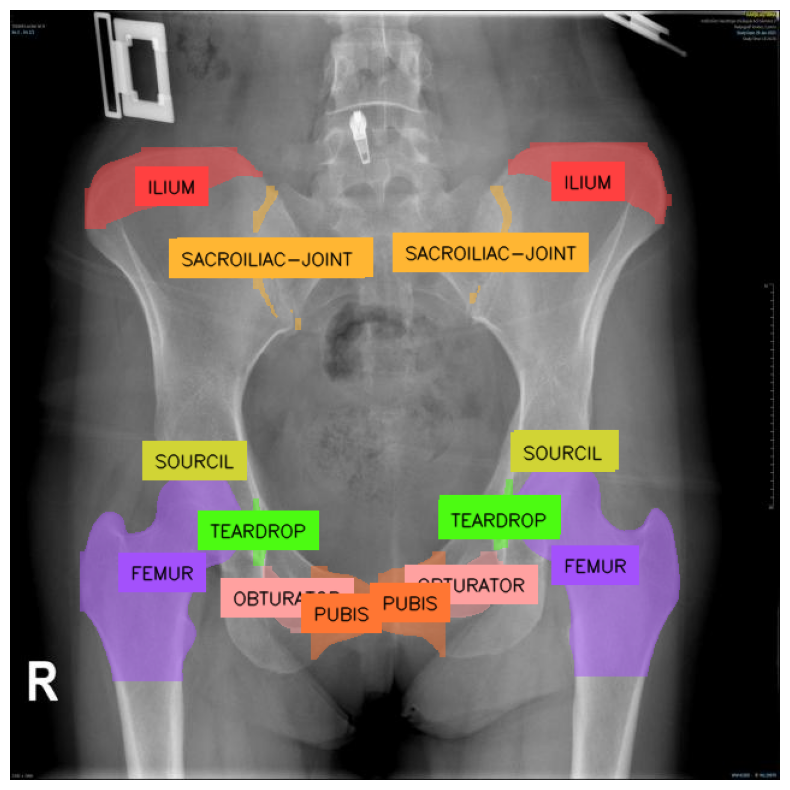

In this article, we'll explore a medical use case by retraining YOLO11 on the Pelvis X-ray dataset from Roboflow Universe. You can access the full code in this Notebook. You can use any dataset you want.

- Medical Diagnosis: The model can assist physicians in diagnosing pelvis-related conditions, such as fractures or degenerative diseases, in areas like the Iliac, Obturator, Femur, Teardrop, Pubis, and Supracetabular regions, helping expedite treatment.

image = cv2.imread(test_set_loc + random_test_image)Notice that some classes are in Latin, and some in Turkish. Let's change it to Latin & English.

name_dictionary = {

"SUORCIL": "SOURCIL",

"SAKRO-ILIAK-EKLEM": "SACROILIAC-JOINT",

"ILIAK": "ILIUM"

}

detections.data["class_name"] = [

name_dictionary.get(class_name, class_name) for class_name in detections.data["class_name"]

]Now, we can visualize our model predictions:

In this article we've shown how to train the YOLO11 model for instance segmentation. The model started off with knowledge of the 80 COCO classes, yet with the dataset found on Roboflow Universe, we brought it to the field of Medicine, teaching it to segment objects in X-ray image of pelvis. We then deployed it to Roboflow, allowing you to query it from other machines! The full code is available in our Notebook.